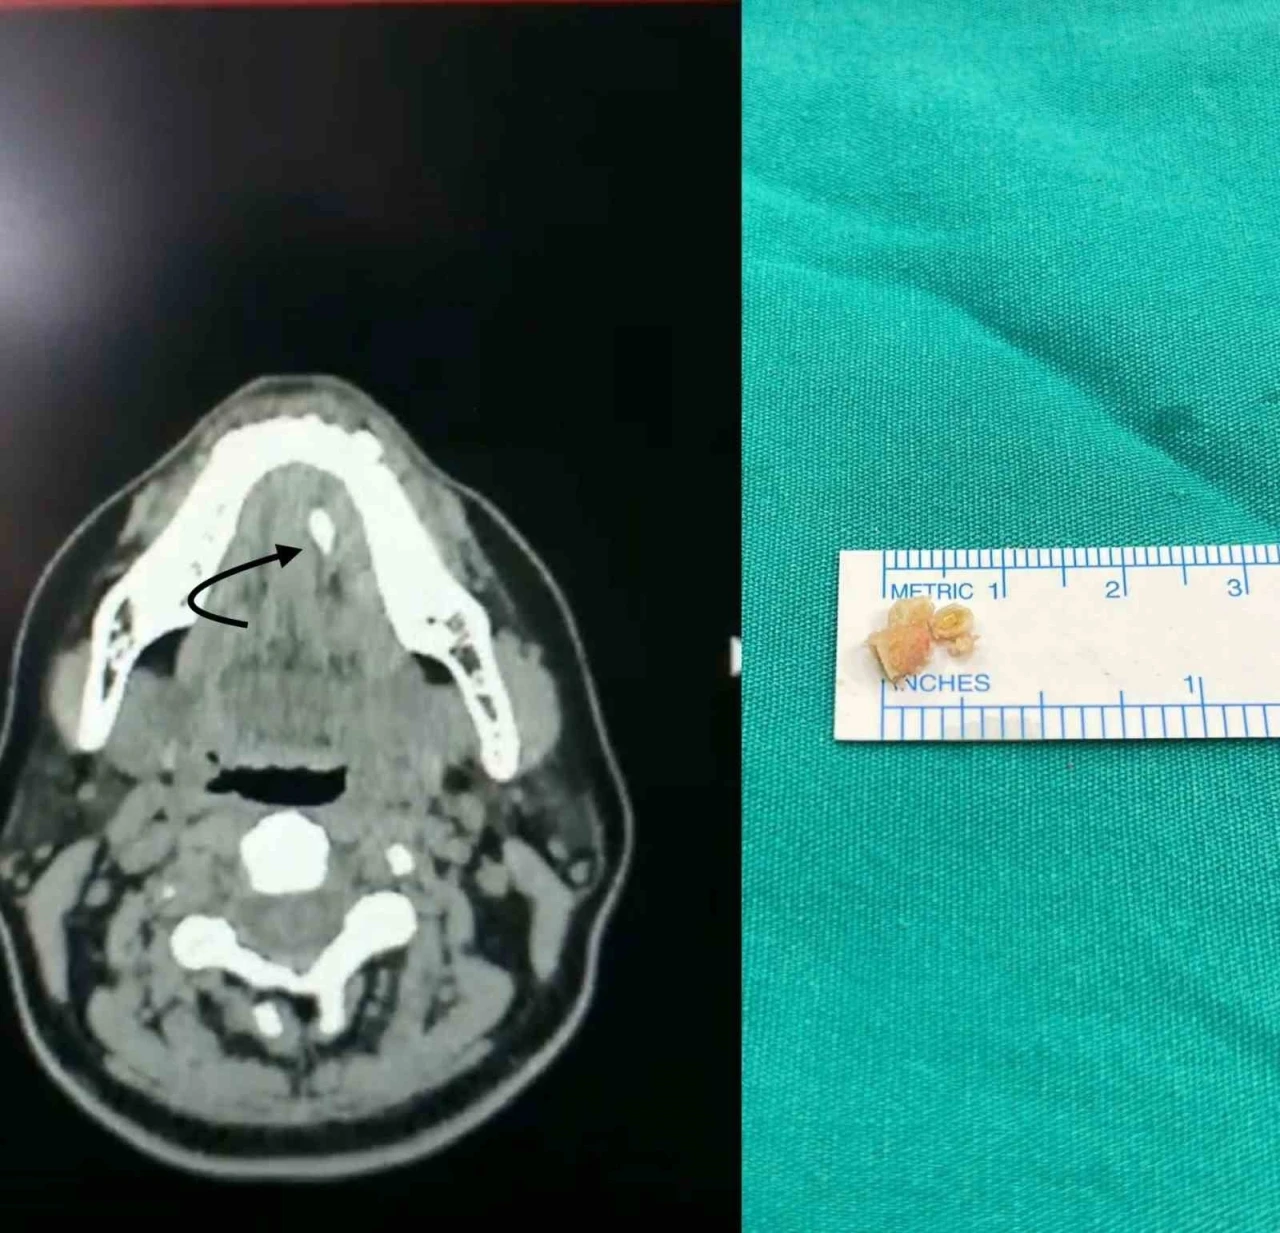

Tükürük bezi taşlarını, çene altında ve yanak arkasında yerleşen tükürük salgısı üreten tükürük bezlerinde veya tükürük bezlerinin ağız içine açılmasını sağlayan tükürük bezi kanallarında görülen taşlar olarak belirten Medicana International Samsun Hastanesi KBB Uzmanı Doç. Dr. Nesrettin Fatih Turgut, “Tükürük bezi taşı tükürük içeriğinin yoğunluğu fazla olduğu için çene altı tükürük bezleri (submandibuler) ve kanallarında ve 30-60 yaş aralığında, erkeklerde daha fazla görülmektedir. Yetersiz sıvı alımı, tükürük salgısının azalmasına neden olan enfeksiyonlar, ilaç kullanımı ve çeşitli enfeksiyonlar ve tükürük bezi kanallarının darlıkları tükürük bezi kanalı içinde taş oluşmasına yatkınlık oluşturur. Bu hastalıkta tipik belirti, taşın var olduğu tarafta yer alan bezde yemek yeme sonrası gelişen şişlik ve ağrıdır. Tükürük salgısının dışarı atılamayıp birikimi, enfeksiyona yatkınlık oluşturur. Bakteriyel tükürük bezi iltihabı dediğimiz hastalık gelişebilir ki bu durumda şikayetler şiddetli hale gelebilir. Etkilenen tükürük bezinin aşırı şişmesi, aşırı hassasiyeti, ağrı ve ateş gelişebilir. Tedavi edilmediği takdirde, hastane yatışı gerektiren ve şiddeti daha fazla olan bir tabloya, derin boyun enfeksiyonuna, ilerleme görebiliriz” dedi. “Taşın büyüklüğü ve konumuna göre cerrahi müdahale söz konusu olabilir”

Şikâyetleri daha hafif olan ve taş boyutları küçük ve tükürük bezi kanalının ucuna yakın yerde yerleşim gösteren hastalarda geleneksel tedaviler önerildiğini dile getiren Doç. Dr. Nesrettin Fatih Turgut, “Ağrı kesiciler fayda sağlar. Bol sıvı tüketimi, ısı uygulaması rahatlama sağlayabilir, bol sıvı tüketimini tüm hastalarımızda önermekteyiz. Aynı zamanda limon gibi ekşi ürünlerin emilmesi tükürük sıvısını artırır ve çok küçük taşların dışarı atılmasını sağlayabilir. Taş boyutunun büyük olması, taşında daha çok beze yakın yerde yerleşmiş olması durumlarında ise cerrahi uygulamaları gündeme gelmektedir. Taş yerleşimi, büyüklüğü etkilenen tükürük bezinin durumu cerrahinin şeklini belirler. Eğer taş tükürük bezi kanalında yer alıyorsa, sialendoskopi olarak adlandırılan kamera sistemi ile yer tespiti ve çıkarma işlemi herhangi bir kesi olmaksızın tercih edilir. Ancak taşın tükürük bezi içerisinde yer alması, boyutunun çok büyük olması durumlarında ise dışardan veya ağız içinden yaklaşım ile cerrahi seçenekleri gündeme gelmektedir” diye konuştu. “Büyük taşlar havalı kırma tekniği kullanılarak küçültülerek çıkarılıyor”

Tükürük bezi kanallarının içindeki en uç bölgelere kadar ulaşabilen bir kamera sistemini kullanarak tükürük kanallarını inceleme yöntemi olan sialendoskopiden bahseden Doç. Dr. Turgut, “Bu sistem, kanal içindeki hastalıkların tanısı ve tedavisi için bir araç sağlar. Kamera sisteminin temel özelliği, tükürük kanalının içini milimetrik boyutlarda kontrol etme yeteneğidir, yaklaşık 1.5 mm’lik bir boyuttan bahsedilmektedir. Bu işlem genel anestezi veya lokal anestezi altında uygulanabilir. Hekimin deneyimi, hastanın sağlık durumu, hastanın uyumuna ve tercihine bağlı olarak tedavi planlaması yapılır. Sialendoskopi, genellikle tükürük kanallarında taş olan hastaların tedavisinde kullanılmaktadır. Ayrıca Sjögren hastalığı, radyoaktif iyot tedavisi almış hastalar ve tekrarlayan tükürük bezi iltihaplarına sahip çocuk hastalarda da bu yöntem uygulanabilir. Sialendoskopi süresi, taşın büyüklüğü ve konumuna bağlı olarak değişebilir. Büyük taşlar havalı kırma tekniği kullanılarak küçültülerek çıkarılır, bu nedenle işlem süresi uzun olabilir. Sialendoskopi sırasında herhangi bir kesi veya dikiş uygulanmaz, bu nedenle işlem sonrasında ağrı veya şikâyet gözlemlenmez. Geçici olarak aynı taraftaki tükürük bezinde şişlik olabilir ancak genellikle bu şişlik 1-2 saat içinde azalır. Hastalar, genellikle aynı gün içinde taburcu edilirler” şeklinde konuştu. “Sialendoskopi ile çıkarılamayan taşlar için açık cerrahi uygulanabilir”

Cerrahi müdahale seçeneği hakkında da bilgi veren Turgut, “Taş boyutunun büyük olması, taşın bez içinde yerleşim göstermesi, sık enfeksiyona bağlı taşın kanala yapışık olması gibi nedenlerden dolayı sialendoskopi ile taşın çıkarılması mümkün olmayabilir. Bu durumlarda açık cerrahi seçeneği gündeme gelir. Eğer taş, kanal içinde yerleşim gösteriyorsa ağız içerisinden kanal üzerinde yapılacak ufak bir kesi ile taşa ulaşılır ve taş çıkarılır. Birkaç dikiş atılarak işlem tamamlanır. Hastalarımız ancak taş tükürük bezi içinde olursa veya tükürük bezi sürekli (kronik) enfeksiyona bağlı olarak işlevini yitirmişse (atrofiye uğramış) tükürük bezi genel anestezi altında çene altından kesi yapılarak tamamen çıkarılır. Ameliyat sonrası 2-3 gün hastane yatışı gerekebilir” ifadelerini kullandı.